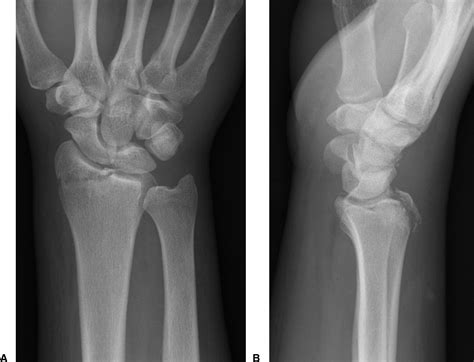

Diagnosing an Ulnar Styloid Fracture

Diagnosing an ulnar styloid fracture typically involves a combination of physical examination and imaging tests. The diagnostic process may include:

• Physical Examination: A healthcare provider will assess the wrist for pain, swelling, and deformity. They may also check the range of motion and stability of the wrist.

• X-rays: These are the primary imaging tool used to confirm the diagnosis. X-rays can show the location and extent of the fracture.

• CT Scan: In some cases, a CT scan may be ordered to provide a more detailed view of the fracture, especially if surgery is being considered.

• MRI: An MRI may be used to assess soft tissue damage, such as ligament injuries, which can accompany an ulnar styloid fracture.